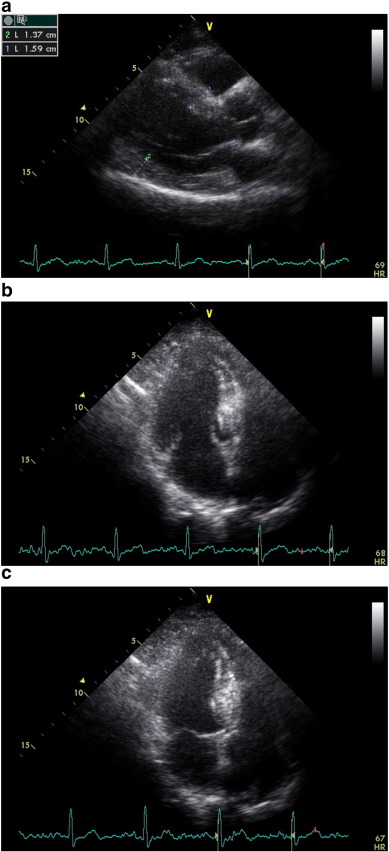

Tissue Doppler Imaging (TDI) permits a quantitative assessment of both global and regional function and timing of myocardial velocities. Pulsed TDI was performed at transducer frequencies of 3.5-4.0 MHz, adjusting spectral Doppler filters until a Nyquist limit of 15-20 cm/s was reached, and using minimal adequate gain. TDI was performed using LV apical 4-chamber imaging and sample volume was subsequently placed on the basal septal (Fig. 1) and basal lateral segment walls in the apical four-chamber view. It is documented that the basal region is associated with the greatest and the most reliable tissue velocity compared with other regions [10]. The imaging angle was adjusted to ensure a parallel alignment of the sampling window with the myocardial segment of interest. Color noise reduction was adjusted, and a color Doppler scanning frame rate of 100 to 140 Hz was used. Myocardial E’ and A’ waves were obtained from LV septal wall, than E/E’ was calculated. Isovolumetric contraction time (IVCT), contraction time (CT), and isovolumetric relaxation time (IVRT) were measured and myocardial performance index (MPI) calculated from the base of septal and lateral walls using the Tei Index which was shown to be valuable in hypertensives [11].

Fig. 1. Evaluation of isovolumetric contraction time, contraction time and isovolumetric relaxation time of the LV septal base by tissue Doppler imaging in a hypertensive patient (MPI = 51). |

Demographic features of 3 groups were pointed out in Table 1. Two dimensional echocardiography was performed in all groups and there was no difference in global LV systolic function. There was no difference in heart rate and blood pressure between the groups during echocardiographic evaluation (Table 2). Mean ejection fraction was similar among the groups, while LV mass index was greater in group II compared with group I and group III (p < 0.0001), (Table 2). We determined thickened walls at parasternal long-axis view in the group II (Fig. 2a). The LV geometric pattern was detected as concentric hypertrophy in this group. (RWT: 0.49 ± 0.8, Table 2). In addition to thickened walls, before functional quantification of regional myocardial tissue using TDI in apical view, we observed LV cavity obliteration during systolic contraction in the patients with LVH (Fig. 2b, c) which is most likely related to thickened walls compared to the other groups.

Fig. 2. a, b, c: End-diastolic parasternal long-axis view, apical LV cavity geometry during diastole and end-systolic LV intracavitary obliteration by remarkable hypertrophied septal wall in an advanced hypertensive patient with left ventricular hypertrophy, respectively. |